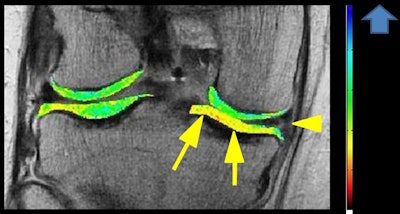

Compositional MRI has become increasingly important for evaluation of the early stage of osteoarthritis before morphological changes that can be depicted on conventional MRI occur, and dGEMRIC is one such technique. In this patient with knee pain, the coronal T1 gadolinium map shows degenerative a horizontal tear of the medial meniscus posterior horn (arrowhead) with low dGEMRIC index (suggesting the presence of compositional abnormality) in otherwise morphologically normal medial tibial plateau cartilage (arrows). Image courtesy of Dr. Daichi Hayashi.Digital x-ray is useful for a basic diagnosis in routine clinical practice and can help establish the structural diagnosis of osteoarthritis, according to Dr. Frank Roemer, radiologist and director of musculoskeletal research in the department of radiology at University of Erlangen in Germany.